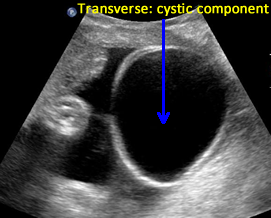

Above. Case 1. 24 3/7 weeks gestation. Sacrococcygeal teratoma. Similar part of the tumor as above showing cysts of various sizes.

Above. Case 1. 24 3/7 weeks gestation. Sacrococcygeal teratoma. The predominant cyst is large and contains anechoic fluid. No polyhydramnios or evidence for fetal hydrops were noted. Delivery occurred at term. Uneventful resection and repair occurred on day 2 of life.

Case 2. 32 1/7 weeks gestation. Sacrococcygeal teratoma. Some transverse views through the predominant cyst demonstrate no solid areas.